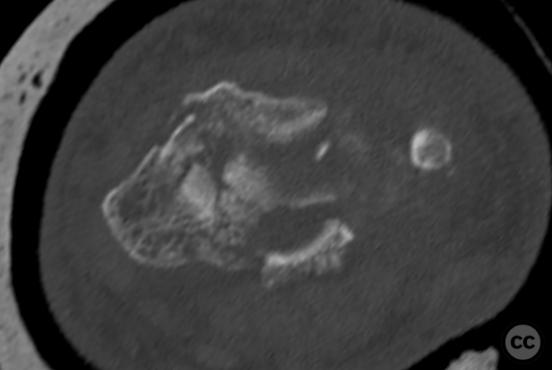

Clinical and radiological findings:  A 72-year-old female sustained a multifragmentary, dorsally displaced distal radius fracture after a fall down stairs. Initial reduction revealed a 180-degree flipped fragment of the volar ulnar articular margin, unreducible by closed means. There was no mention of associated neurovascular compromise or open injury. Radiographs and intraoperative fluoroscopy confirmed the presence of a multifragmentary intra-articular fracture (AO/OTA 23-C3), with a flipped volar ulnar fragment and radial styloid impaction. The distal radioulnar joint alignment was restored postoperatively.

Anatomical surgical approach:  A longitudinal incision was made over the flexor carpi radialis (FCR), zigzagging over the wrist crease. Subcutaneous dissection and incision of the FCR tendon sheath were performed, followed by transection of musculus pronator quadratus fibers along the radial border of the distal FCR. The FCR tendon was retracted ulnarly, and the antebrachial fascia incised. Musculus flexor pollicis longus was identified and retracted ulnarly. The pronator quadratus was incised along its radial border and the watershed line, then elevated subperiosteally to expose the distal radius. Extended distal release of the FCR allowed wide exposure of the ulnar aspect of the lunate facet and volar lip. The flipped volar ulnar fragment was de-rotated and provisionally fixed with a Kirschner wire. Ligamentotaxis for radial styloid reduction was achieved using Kirschner wires in the scaphoid and distal radius, with a wire spreader applied for distraction. Provisional fixation was achieved with multiple Kirschner wires. A mini-fragment T-plate, cut and shaped as a hook plate, was applied to the volar ulnar lip fragment, fixed with bicortical screws, and used to engage dorsal fragments. The radial styloid was addressed with a contoured T-plate, similarly fixed with bicortical locking screws. Final multiplanar fluoroscopy confirmed anatomical reduction and hardware placement.

The flipped volar ulnar articular margin fragment was irreducible by closed means due to capsular attachment and required direct open de-rotation and fixation. The impaction and proximal displacement of the radial styloid fragments were challenging due to persistent traction from musculus brachioradialis and scaphoid pressure; ligamentotaxis using Kirschner wire spreader over the scaphoid facilitated reduction. Fragment-specific fixation was necessary: a custom-shaped hook plate for the volar ulnar lip fragment provided stable fixation and prevented dorsal instability, while a separate T-plate addressed the radial styloid. Bicortical locking screws were used to secure both plates, with some screws engaging dorsal fragments from the volar side. Careful adaptation of pronator quadratus over hardware minimized risk of musculus flexor pollicis longus irritation. Additional suture stabilization of radiocarpal ligaments to pronator quadratus provided secondary ligamnetal support.